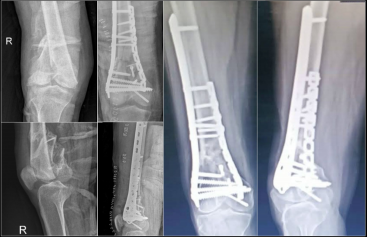

2.双钢板固定

目前,双钢板固定或钉板联合固定形式已成为大多数老年股骨远端骨折的首选治疗方法。

这种固定方式能满足老年股骨远端骨折对稳定性的更高要求,尤其适用于关节内骨折和伴有干骺端粉碎的骨折类型。其额外增加的内侧锁定钢板提升了整体结构的生物力学稳定性,提供的抗扭转稳定性远高于单一外侧钢板。

股骨远端外侧接骨板

型号:DCA24

规格:5-13孔

长度:156-316mm